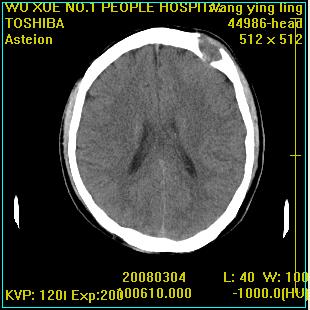

标题: CT12023:女,50岁,头部包块二月,伴轻微头痛,不伴发热。 [打印本页]

标题: CT12023:女,50岁,头部包块二月,伴轻微头痛,不伴发热。

这种病例还是比较多见,起源于颅骨板障,向颅内和颅外生长,考虑血管瘤或嗜酸性肉芽肿,要是有增强ct就好了。

多发溶骨性破坏,骨嗜酸性肉芽肿可能,转移瘤待排除,建议进一步检查。